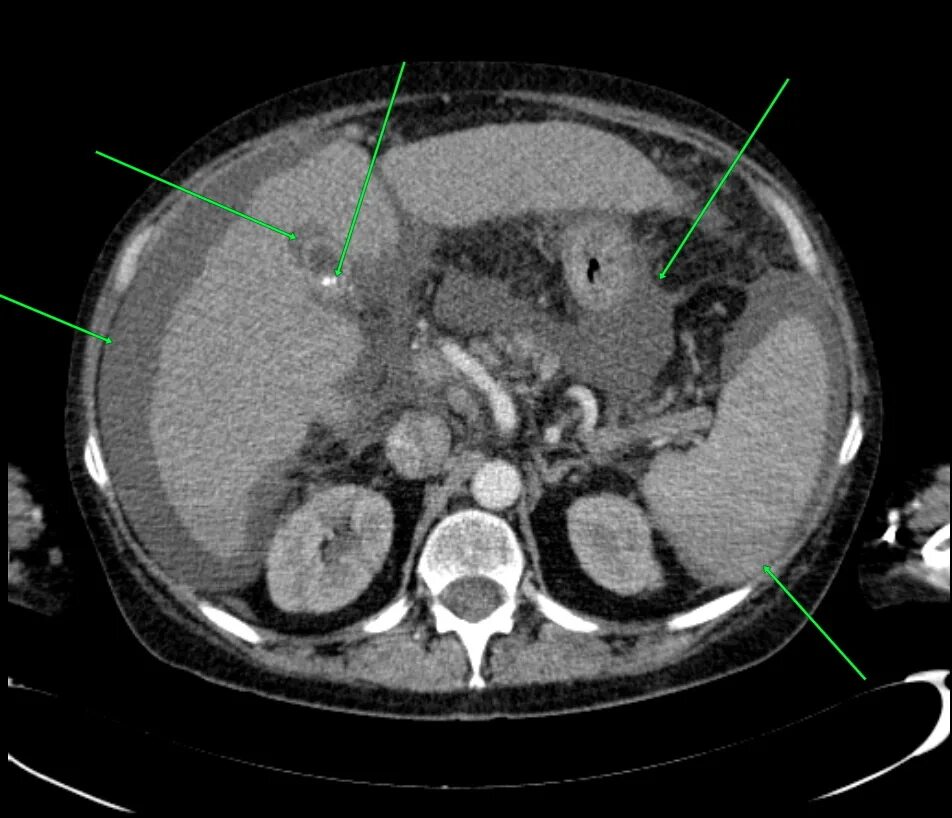

Кт обп омт с контрастированием